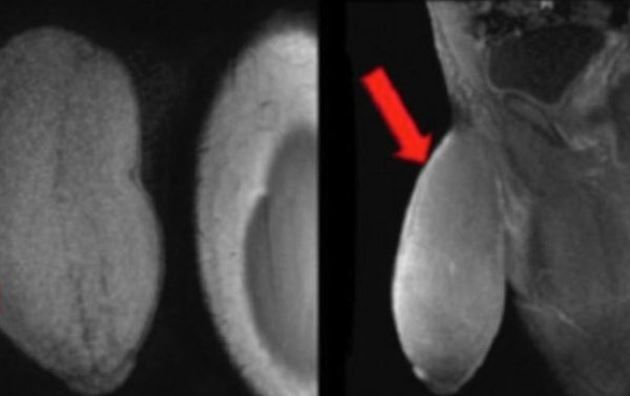

Πριν την χειρουργική επέμβαση οι γιατροί είπαν, σύμφωνα με την MailOnline, ότι το πέος του είχε το μέγεθος μίας μπάλας του ράγκμπι ή ενός γκρέιπφρουτ και ότι ήταν η πρώτη φορά που κάποιος ζητούσε να μικρύνει το πέος του.

Ο 17χρονος, παραπονιόταν συνεχώς μιας και δεν μπορούσε να κάνει όσα έκαναν οι συνομήλικοι του, ενώ με το παραμικρό πονούσε.

Μάλιστα, όπως λέει το πέος του ήταν τόσο μεγάλο που δεν άλλαζε κάτι όταν είχε στύση ενώ είχε φρικτούς πόνους.

Σύμφωνα με τους γιατρούς η εγχείρηση ολοκληρώθηκε επιτυχώς.